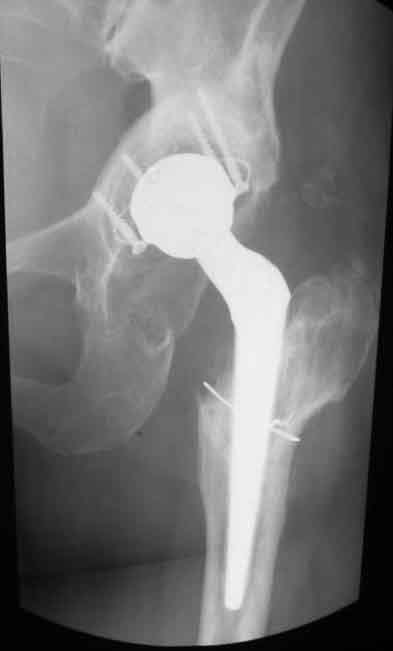

Уважаемые коллеги. Хотелось бы услышать мнения и советы по представляемому случаю. Пациентка 45 лет. Бесцементное эндопротезирование левого тазобедренного сустава 6 лет назад (впадина RM, Mathys, металл-металл, ножка Зульцеровская). За 10 лет до протезирования – коррегирующая остеотомия бедренной кости, которая не срослась в течение года до удаления пластины, а затем срослась в течение 3 месяцев иммобилизации в кокситной повязке. После протезирования получилось наблюдать пациентку почти постоянно, поскольку через 2 года синтезировал ей лодыжки на оперированной стороне, затем, через несколько месяцев удалил фиксаторы, а в 2009г. резецировал мениск на противоположной стороне. Боли все эти годы не беспокоили. Пациентка чуть выше среднего роста, вес тела нормальный. Физические нагрузки переносила хорошо. Работает на 7 этаже без лифта. Год назад экстирпация матки по поводу лейомиомы больших размеров. Несколько месяцев назад появились боли в области левого тазобедренного сустава. При рентгеновском и КТ исследованиях (июль с.г.) – нестабильность тазового компонента. От предложенной замены протеза пациентка на тот момент, слава богу, отказалась. Через какое то время боли в области левого тазобедренного сустава практически полностью прошли, а около 2 месяцев назад появилось ощущение патологической подвижности таза и боли в паху справа, которые через некоторое время уменьшились, а потом снова усилились после значительных физических нагрузок (много ходила по песку на пляже, носила тяжести). Ежедневно принимала диклофенак. На рентгенограммах – переломы правой лонной кости. Сейчас госпитализирована из-за болей в паху справа. Боли слева не беспокоят. На фоне снижения нагрузок в стационаре боли значимо уменьшились. Способна ходить без средств дополнительной опоры.В анализах крови чуть повышены трансаминазы и гамма-ГТ, моча без особенностей.

Вопросы: -правильно ли я расцениваю переломы как стрессовые на фоне неполноценного таза (pelvic insufficiency stress fractures)? -Можно ли так же расценить ситуацию на стороне протеза и, соответственно, не торопиться с ревизией, рассчитывая на вторичную стабилизацию? Уж больно не хочется менять ножку. -Если думать о ревизии, то когда? На представленных снимках тазобедренный сустав до и сразу после операции, затем 2 снимка 2009г., когда ничего не беспокоило, затем КТ 2-х месячной давности и вчерашние рентгенограммы обоих тазобедренных суставов.

Сергей, очень возможно, что перелом и стрессовый, но мне видится, что его причина в нестабильности чашки. Дело в том, что в отличии от ножек, чашка при своей дестабилизации болит гораздо меньше и больные терпят до последнего.

При сравнении рентгенограмм можно увидеть насколько чашка переместилась от места своего первичного расположения. От опрокидывания ее удерживают конструкционные элементы "рожки". Без них ситуация, возможно, уже была бы катастрофической (чашка в тазу). Думаю надежды на вторичную интеграцию, могут быть обмануты и ревизии не избежать.